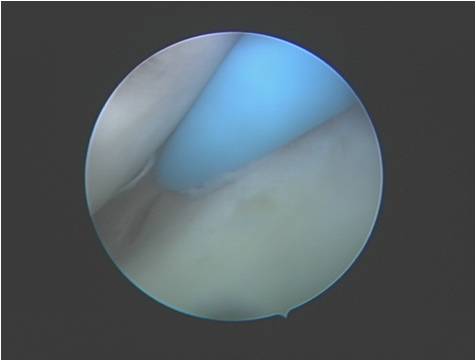

肩关节镜手术